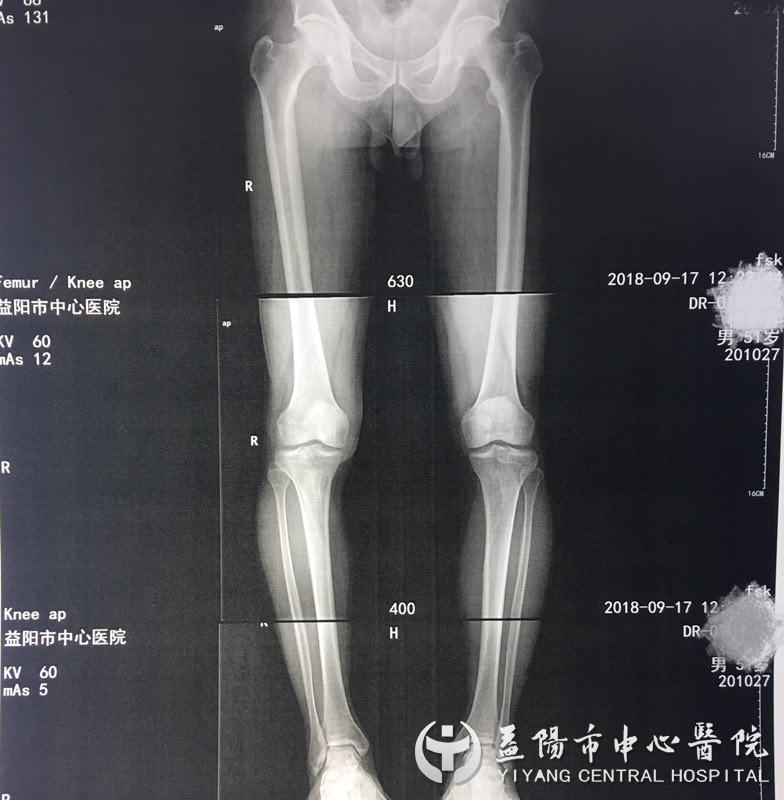

51岁的杨先生深受膝关节疼痛的折磨2年有余,期间频繁出现右膝关节疼痛不适,劳累后加重,几经治疗后,症状没得到控制,近几个月来右膝部疼痛明显加重,伴行走困难,甚至开始累及到左膝关节,曾多次辗转多家医院治疗,很多医院都建议进行关节置换,因个人经济情况及自身条件限制,杨先生暂时不考虑换关节。抱着试试看的想法,杨先生来到益阳市中心医院骨外科二病区就诊,经X片检查显示:右膝关节退行性变,膝关节内侧间隙略变窄,被诊断为“右膝关节骨性关节炎”。

骨外科二病区关节团队考虑到患者日后仍需从事繁重的体力劳动,经过团队反复讨论、研究,决定用3D打印技术辅助下行胫骨高位截骨术。先通过术前在计算机三维模型上精确规划截骨线及骨块复位,并通过计算机软件设计制作能够与胫骨近端骨质的三维形态完全匹配的数字化导板,并通过3D打印技术打印出来,提高手术精确性。完成详细的术前准备后,骨外科二病区关节团队为杨先生实施了手术,手术顺利进行仅耗时三十分钟左右,术后恢复良好,术后第2天就可以在助步器辅助下下地行走。他逢人就夸关节手术技术高、技术强,不仅缓解了疼痛,还保住了他的膝关节。3D打印辅助下胫骨高位截骨术是目前治疗胫骨近端畸形的一种有效手术方法。